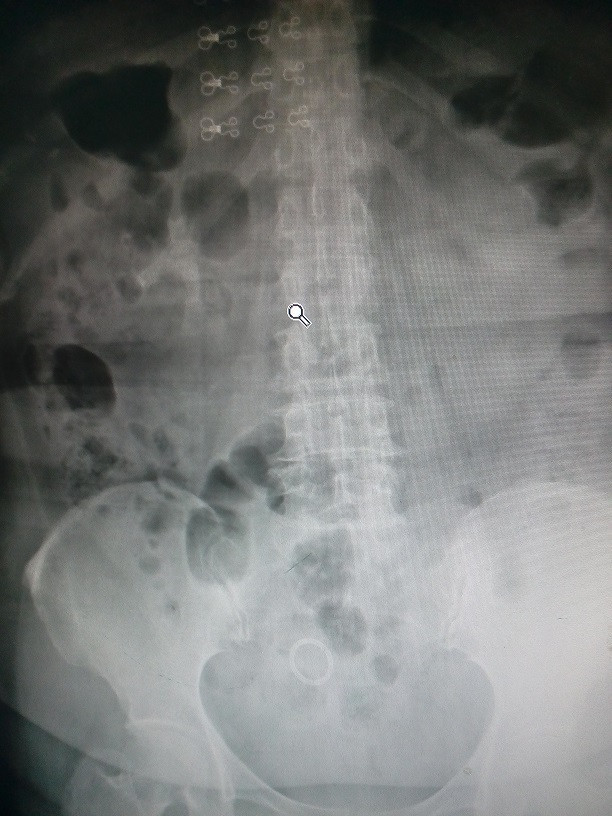

患者主因“体检发现右肾结石、右肾萎缩一月余“入院;患者自诉一月前体检时发现右肾结石、右肾萎缩,平日无腰疼,发热,无活动后肉眼或镜下血尿;无恶心、呕吐;当时因无明显症状未行治疗。后至我院复查,建议其手术治疗,门诊以“右肾结石、右肾萎缩”收住入院。

查体:无异常。 辅助检查:1、泌尿系CT平扫:右肾结石、右肾萎缩。 2 、泌尿系彩超:右肾轮廓不清、大小约4.9X1.8cm,实质厚0.3cm,考虑右肾萎缩、多发性结石。 3、行分肾功能示:肾功能参数:GFR(ml/min):左侧:53.67;右侧:4.88;总:58.56(右肾近无功能,左肾功能轻度代偿性增高。)

1、右肾结石 2、右肾萎缩。 2、治疗:腹腔镜下右肾切除术